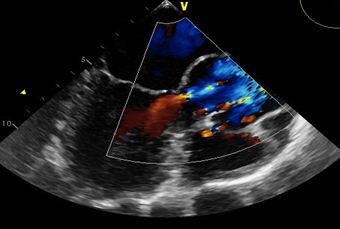

A 42-year-old man presented to the ED after multiple episodes of difficulty in speaking. He was unable to formulate his speech but was aware of what he wanted to say. Three years earlier, the patient had a deep venous thrombosis that was treated with anticoagulation. The transesophageal echocardiogram indicated patent foramen ovale (PFO).